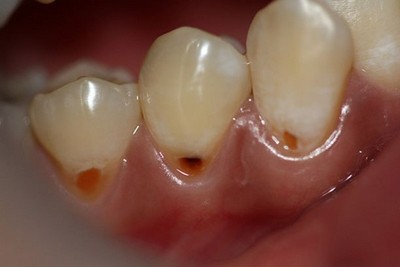

Своевременное и безотлагательное лечение кариеса — основная профилактика пульпита. Но даже, на первый взгляд, благополучно запломбированные зубы не являются поводом игнорировать регулярные профилактические осмотры.

Если произошёл скол эмали, реставрацию зуба необходимо произвести в сжатые сроки.

Систематическое воздействие холодной, горячей и кислой пищи в этом случае достаточно быстро вызывает пульпит.